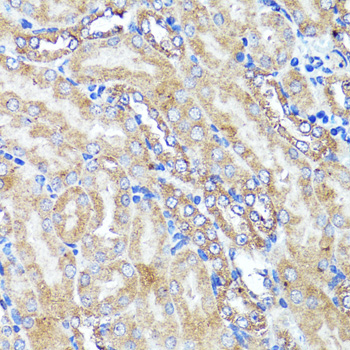

| Application: | WB IHC |

| Application: | WB IHC |

| Recommended Dilution: | WB 1:500 - 1:2000 IHC 1:50 - 1:100 |